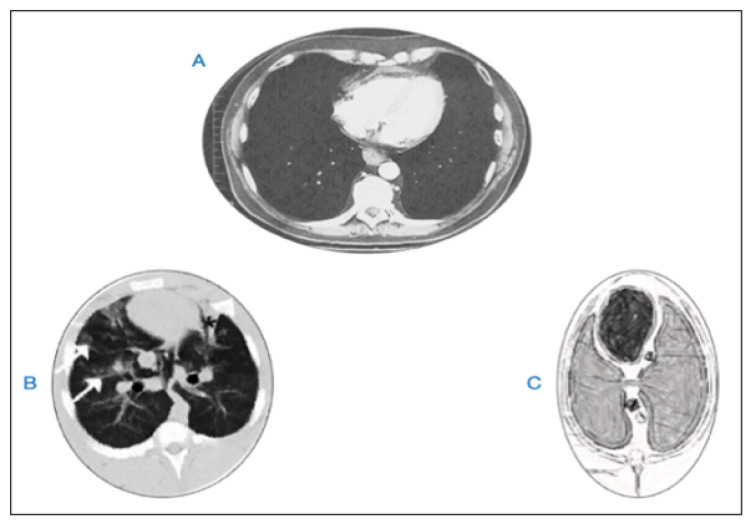

Cardiopulmonary resuscitation (CPR) remains controversial with dismal outcomes for cardiac arrest (CA) victims. Inadequate organ perfusion and frequent CPR-related trauma most likely occur due to inappropriate adaptation to hemostatic conditions, electrophysiology, cardiotorsal anatomy, and thoracic biomechanics. Alternatively, we propose a new technique compromising chest compressions through the 5th intercostal space while placing the victim in the left lateral decubitus position with wrapped abdomen and raised legs, allowing to: bypass the sternal barrier, refill the heart, and then recoil-rebound the chest (3R /CPR), within the axis of the cylindrical ribcage. Our goal is to evaluate the technique following its necessary application on two drowning victims. It seems that, 3R/CPR adapts the pathophysiological conditions of CA victims promoting a less traumatic return of spontaneous circulation (ROSC), making it worthy of further investigation and study.